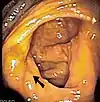

Imagine endoscopică a cecumului, săgeata arătând către valva ilocecală